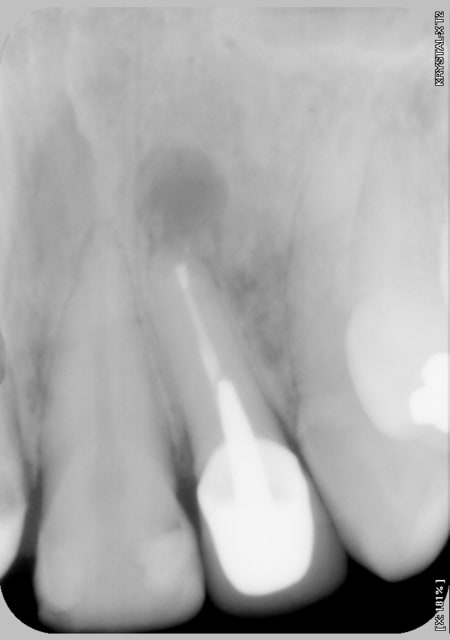

Sourire gingivale a mort, une CCM faite l'année derniere.

Morphotype epais et une bonne bande de gencive keratinisé.

Tout ce dont j'avais besoin pour changer un peu de la "routine" des resections apicales.

Mais apres analyse des photos jme suis dit que j'aurais du moins m'emballer sur la longueur !